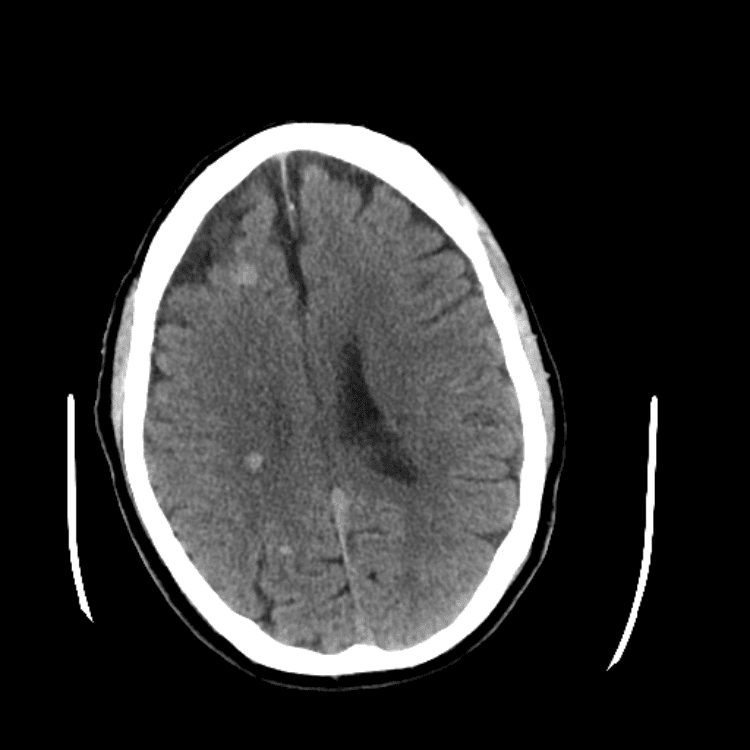

Nontraumatic Brain

Classic